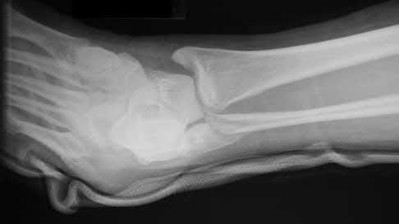

2. # A 35-year-old woman is involved in a head-on collision while driving. Initial radiographs are shown in Figures 8a and 8b. Injury to what vessel increases the risk for osteonecrosis of the injured bone?

5. Artery of the tarsal sinus Corrent answer: 4

The patient has a Hawkins type III talar neck fracture-dislocation with a risk of osteonecrosis ranging from 69% to 100%. Anatomic studies have shown that the artery of the tarsal canal supplies the lateral two thirds of the talar body.

The other vessels listed provide no significant contribution to the talus.